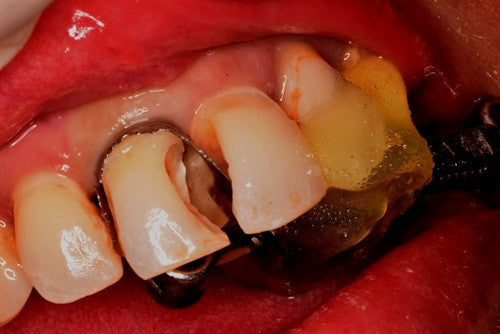

Recurrent caries under crown - "Thinking outside of the box" by Dr. Ahmad Fayad

Posted on March 22 2023

Introduction: This case was completed by Dr. Ahmad Fayad of Lessard Dental located in Alberta, Canada. Food impaction area that caused massive carious lesion at the distal of the lower... Read More